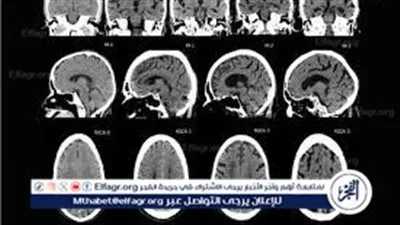

2. ضمور المخ

ضمور المخ

ضمور المخ.. درجات الإصابة به وطرق علاجه

"مرض السكتات".. ما لا تعرفه عن "ضمور المخ" عند الأطفال